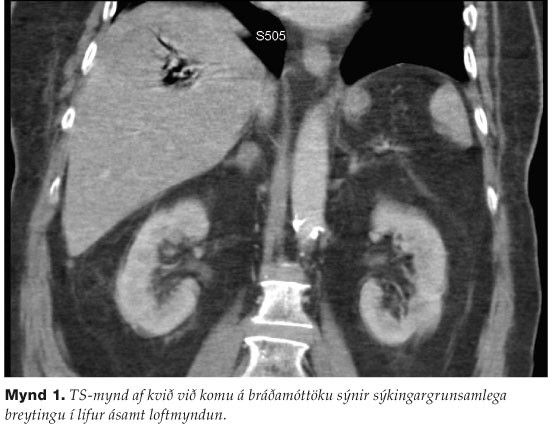

Settur var þvagleggur og kom þá lítið af dökkrauðu þvagi. Strimilpróf sýndi 4+ af sykri og 3+ af ketonum. TS-mynd af kvið sýndi loftmyndun í lifur (mynd 1). Hafin var meðferð með insúlíndreypi og vökva, teknar ræktanir og sjúklingur settur á Ampicillin, Cefuroxím og Metronidazól í æð. Útskilnaður var einungis 15 mL fyrstu fjórar klukkustundirnar og var hann því tengdur við nýrnaskilunarvél. Endurtekin blóðprufa sýndi hvít blóðkorn 21,3 x109/L, hemóglóbín 70 g/L, hematókrít 0,19 og blóðflögur 607 x109/L. Hann fékk samtals fjórar einingar af rauðkornaþykkni og sjö einingar af blóðflögum. Hann féll í blóðþrýstingi, var barkaþræddur og lagður í öndunarvél. Blóðsýni var afar óeðlilegt séð með berum augum, sermi svartleitt (mynd 2). Daginn eftir greindust gram-jákvæðar staflaga bakteríur í blóðræktun.